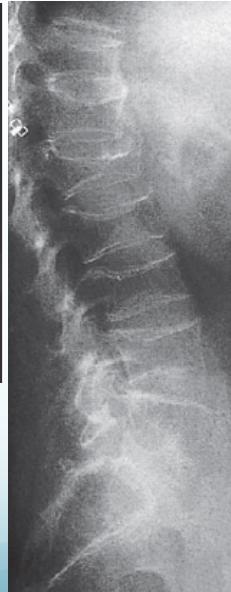

- Biconcave vertebrae & compression fractures

Vertebral bodies are biconcave